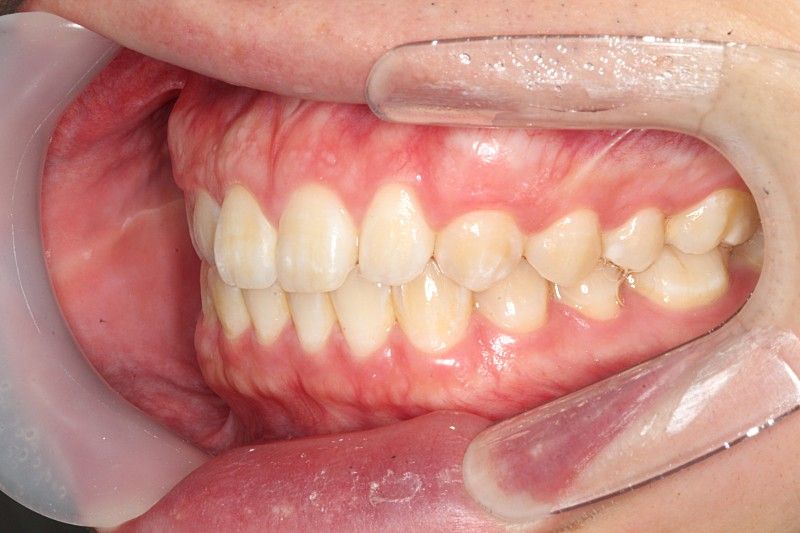

윗니가 앞으로 나오는 정도는 사람마다 다릅니다. 지금 사진상으로 보아 윗니가 앞으로 나온 양이 조금 적어 보이나

정상 범위입니다. 다만 오른쪽 작은 앞니(측절치)는 아랫니가 앞으로 나온 반대교합 입니다.

앞니 교합이 좋진 않으신거 같습니다. 왼쪽치아들은 그래도 잘 물리는데 오른쪽 치아들의 교합이 좋진 않네요.